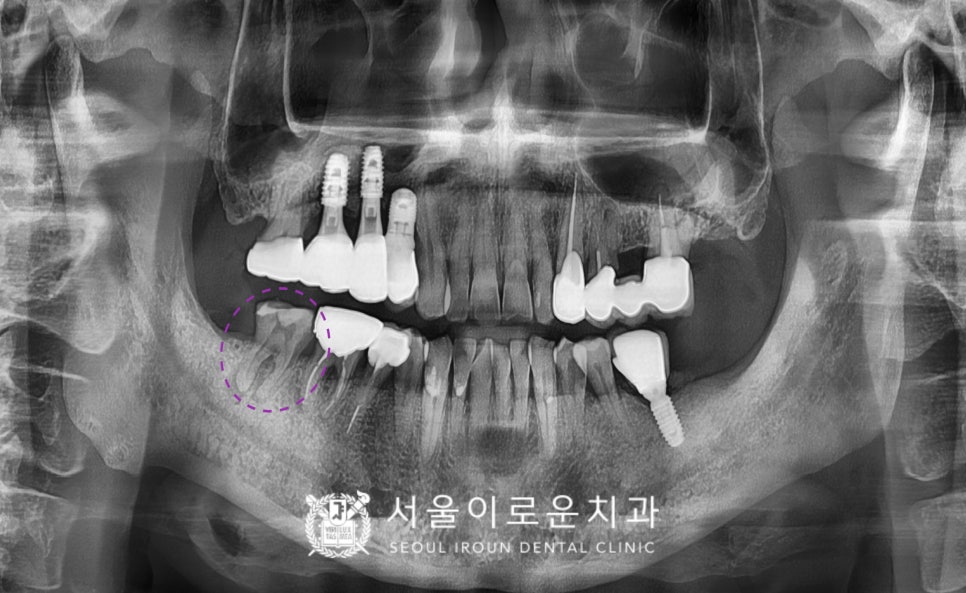

오른쪽 위 어금니 부위에는

기존 브릿지를 컷팅 한 후

두 번째 작은 어금니(#15)를 발치하였으며,

남아있는 잔존 뼈가 적어

임플란트 식립할 공간 확보가 어려워

상악동 막을 들어 올려 뼈이식을 진행한 후

임플란트 식립을 진행하는

상악동 거상술을 동반하여

임플란트 즉시 식립을 진행하였습니다.